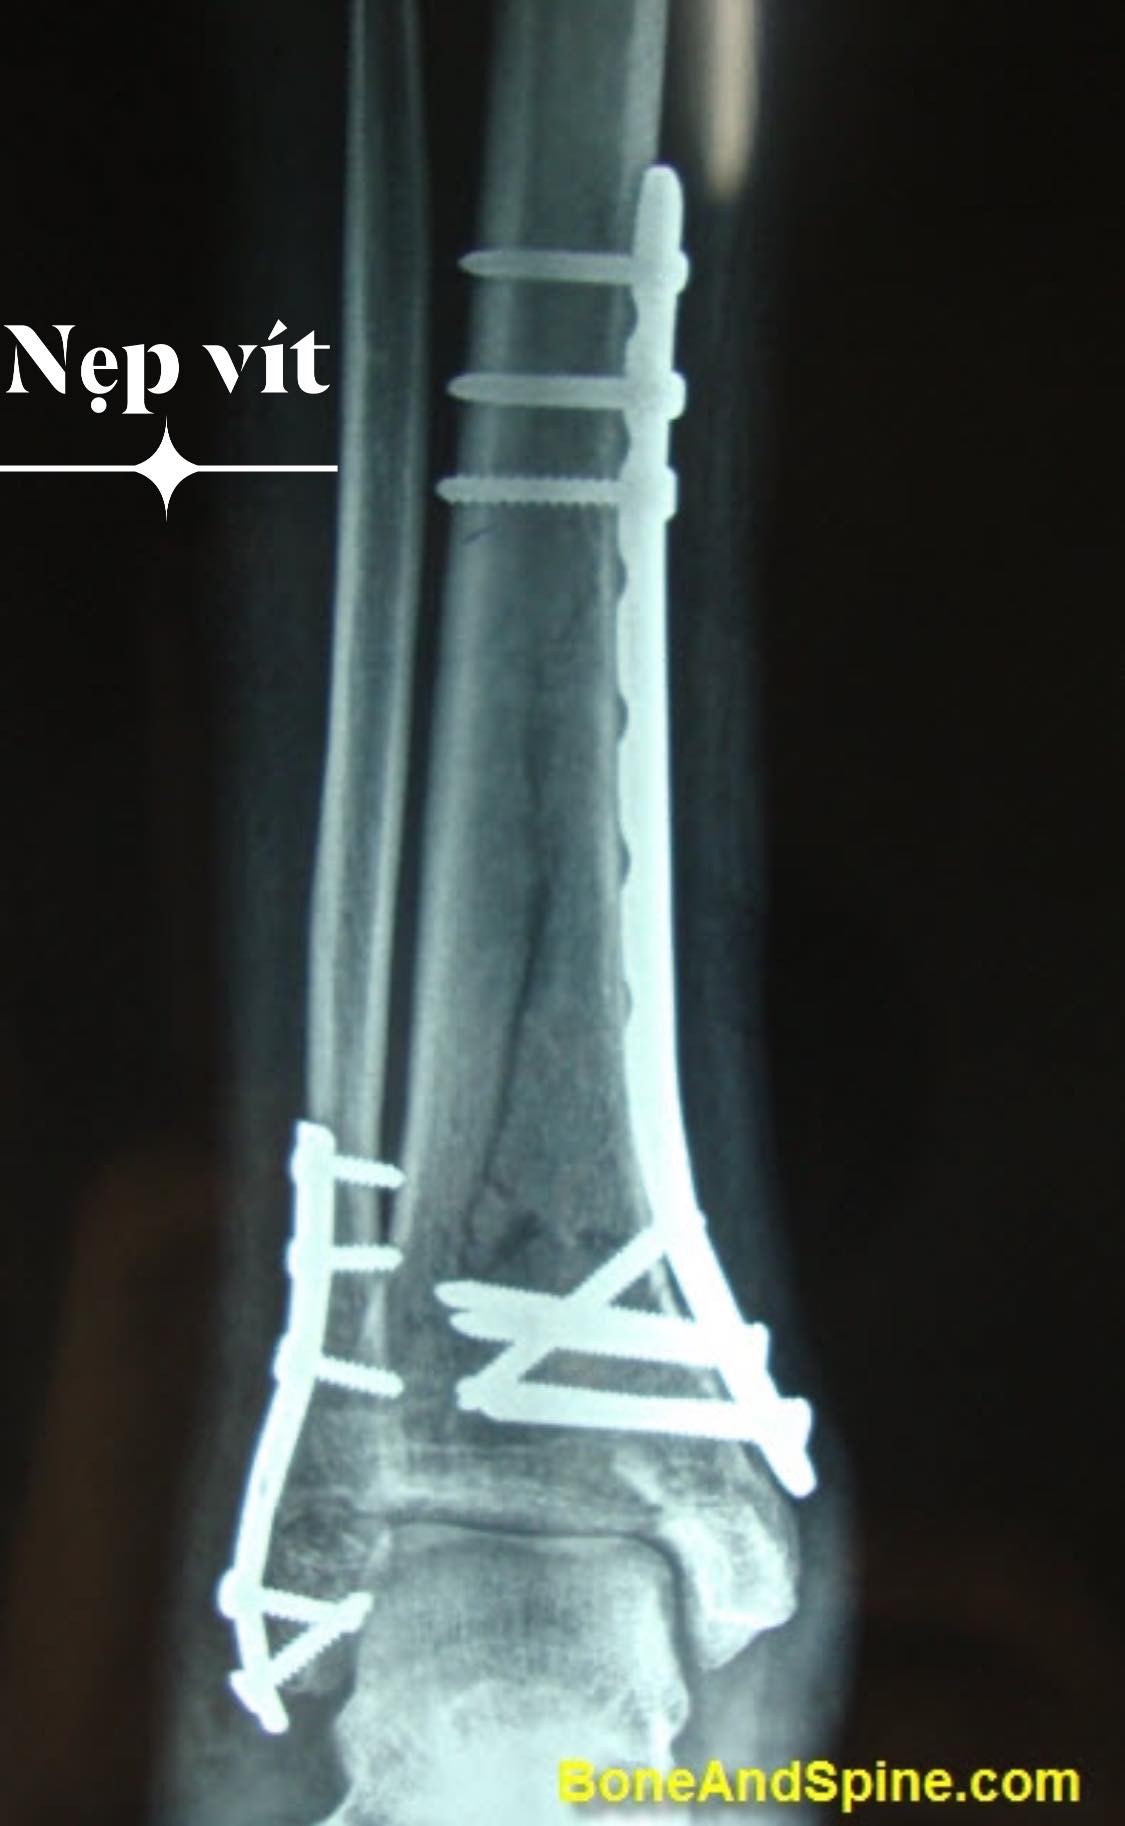

- Kết hợp xương chày = nẹp vít (plate) hoặc đinh nội tuỷ có chốt (Intramedullary locking nail)

- Kết hợp xương mác = nẹp vít hoặc kim Kirschner

Về lâu dài: Lấy nẹp vít ra sau 2-3 năm

Nếu để nẹp lâu quá: Có thể dẫn đến loãng xương dưới nẹp, dễ gãy xương 2 đầu nẹp

Nếu là đinh nội tuỷ: Không gây loãng xương dứoi nẹp, có thể để lâu hơn, có thể đau trước gối làm hạn chế chạy nhảy.